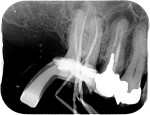

Root canal treatment can be a difficult procedure for the dentist to perform to the internal complexity of the canal system.

The first appointment is the cleaning out process, you will be given local anaesthetic before starting treatment and ensured you are fully numb before commencing. A rubber sheet will be placed where possible to ensure no filling is leaked into the mouth and no bacteria enters the space we are working in. This sheet can be removed at any point but most patients find this reassuring and comfortable. The filling will be removed with water spray and the canals will be accessed and disinfected in this appointment, this is no harder than a simple filling.

On the second appointment we do the same procedure with local anaesthetic and disinfect and prepare the canals, once we are happy with our preparation the canals are sealed with rubber points and a sealant into each canal. Radiographs may be taken to check our progress before sealing. A temporary restoration may be placed depending if the tooth requires further treatment.

A follow up x-rays is normally taken a year after completion to ensure any areas of infection are healing.